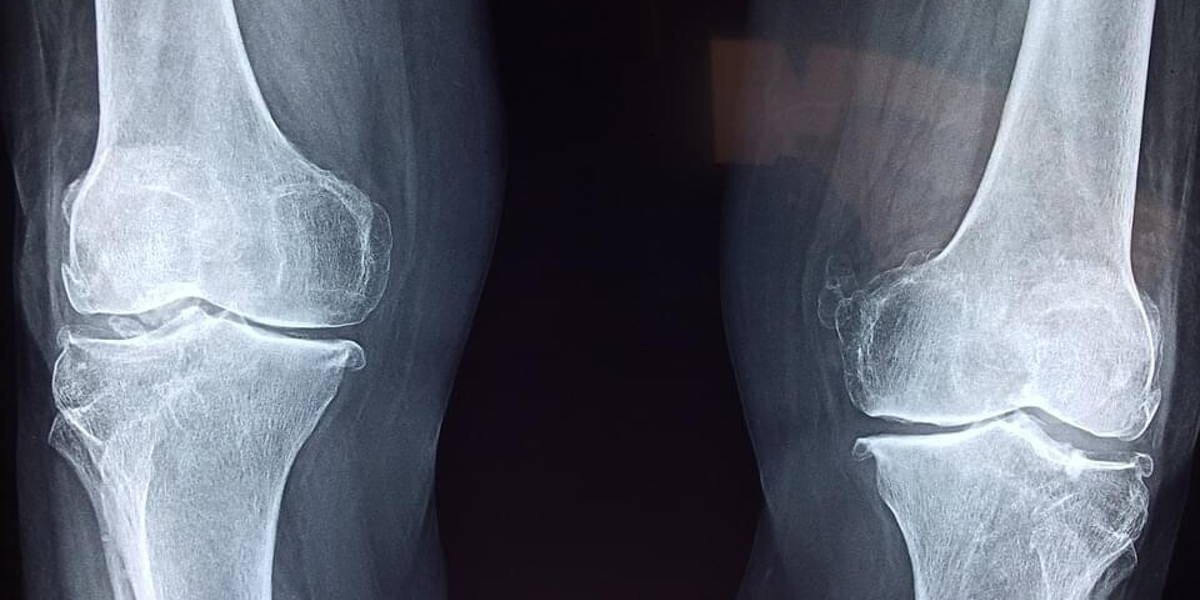

Hy2Care, een Nederlandse startup die hydrogeltechnologie voor kraakbeenreparatie heeft ontwikkeld, laat weten dat het 3,7 miljoen euro aan financiering opgehaald. Met de financiering wil de spin-off van de Universiteit Twente de technologie voor diergeneeskundig gebruik verder commercialiseren en menselijke proeven initiëren. De serie A-ronde werd geleid door Brightlands Venture Partners, daarbij ondersteund door verschillende co-investeerders en de Nederlandse Arthritis Society (ReumaNederland, voorheen Reumafonds).

Hy2Care, opgericht in 2014, richt zich op de ontwikkeling en commercialisering van een nieuw hydrogelapparaat dat naar eigen zeggen ‘indrukwekkende resultaten’ heeft opgeleverd bij het herstellen van kraakbeendefecten. De Hydrogel-technologie, ook wel omschreven als een 'injecteerbare pleister', moet snelle reparatie mogelijk maken van acute kraakbeendefecten als gevolg van vallen, ongevallen en sportblessures.

De procedure belooft een grote verbetering in functionaliteit op de korte termijn en pijnverlichting in vergelijking met de huidige methoden - zoals arthroscopisch debridement en microfracturering. Bovendien kan de hydrogel worden gebruikt tijdens de eerste arthroscopische kijkprocedure, waardoor de behoefte aan secundaire chirurgie en revalidatie afneemt. Minder en minder ingrijpende ingrepen zullen bij menselijke toepassingen ook opnameduur beperken en revalidatie versnellen.

"Als het niet goed wordt behandeld, zal ongeveer 80 procent van deze defecten leiden tot artrose, wat uiteindelijk ernstige pijn veroorzaakt en zeer invasieve oplossingen nodig heeft, zoals kunstmatige knieprothesen. Door een betere vroege reparatie te bedenken, voorkomen we veel ongemak voor patiënten en nemen we ook aanzienlijke kosten voor de gezondheidszorg weg."